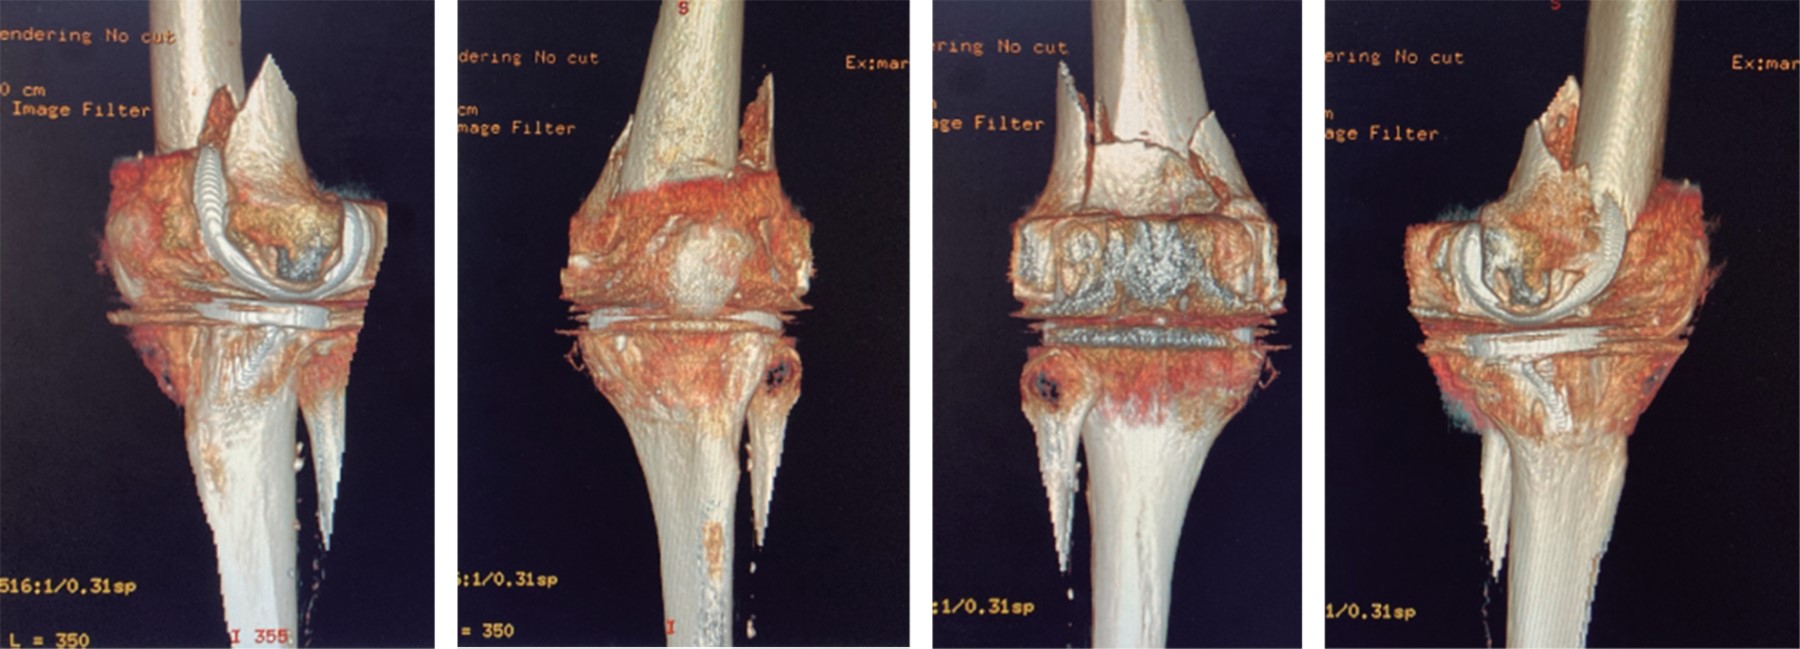

Figure 3